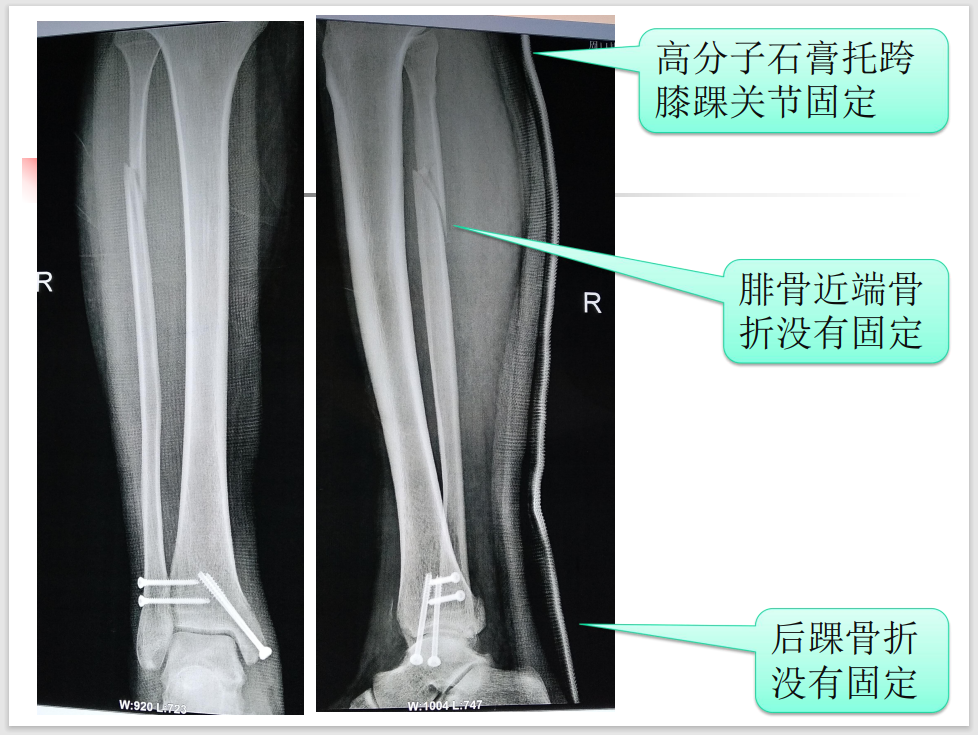

特殊类型踝关节骨折虽然临床少见,但是其诊断、治疗不准确会带来诸多不良后遗症,以致踝关节功能障碍,今天我们就来学习一下Maisonneuve 骨折!